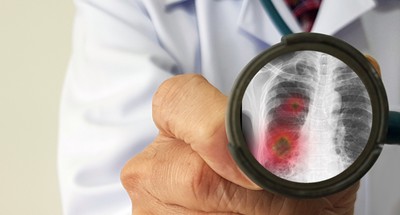

Tak Koronawirus Wplywa Na Pluca Zdjecie Chorej Pacjentki